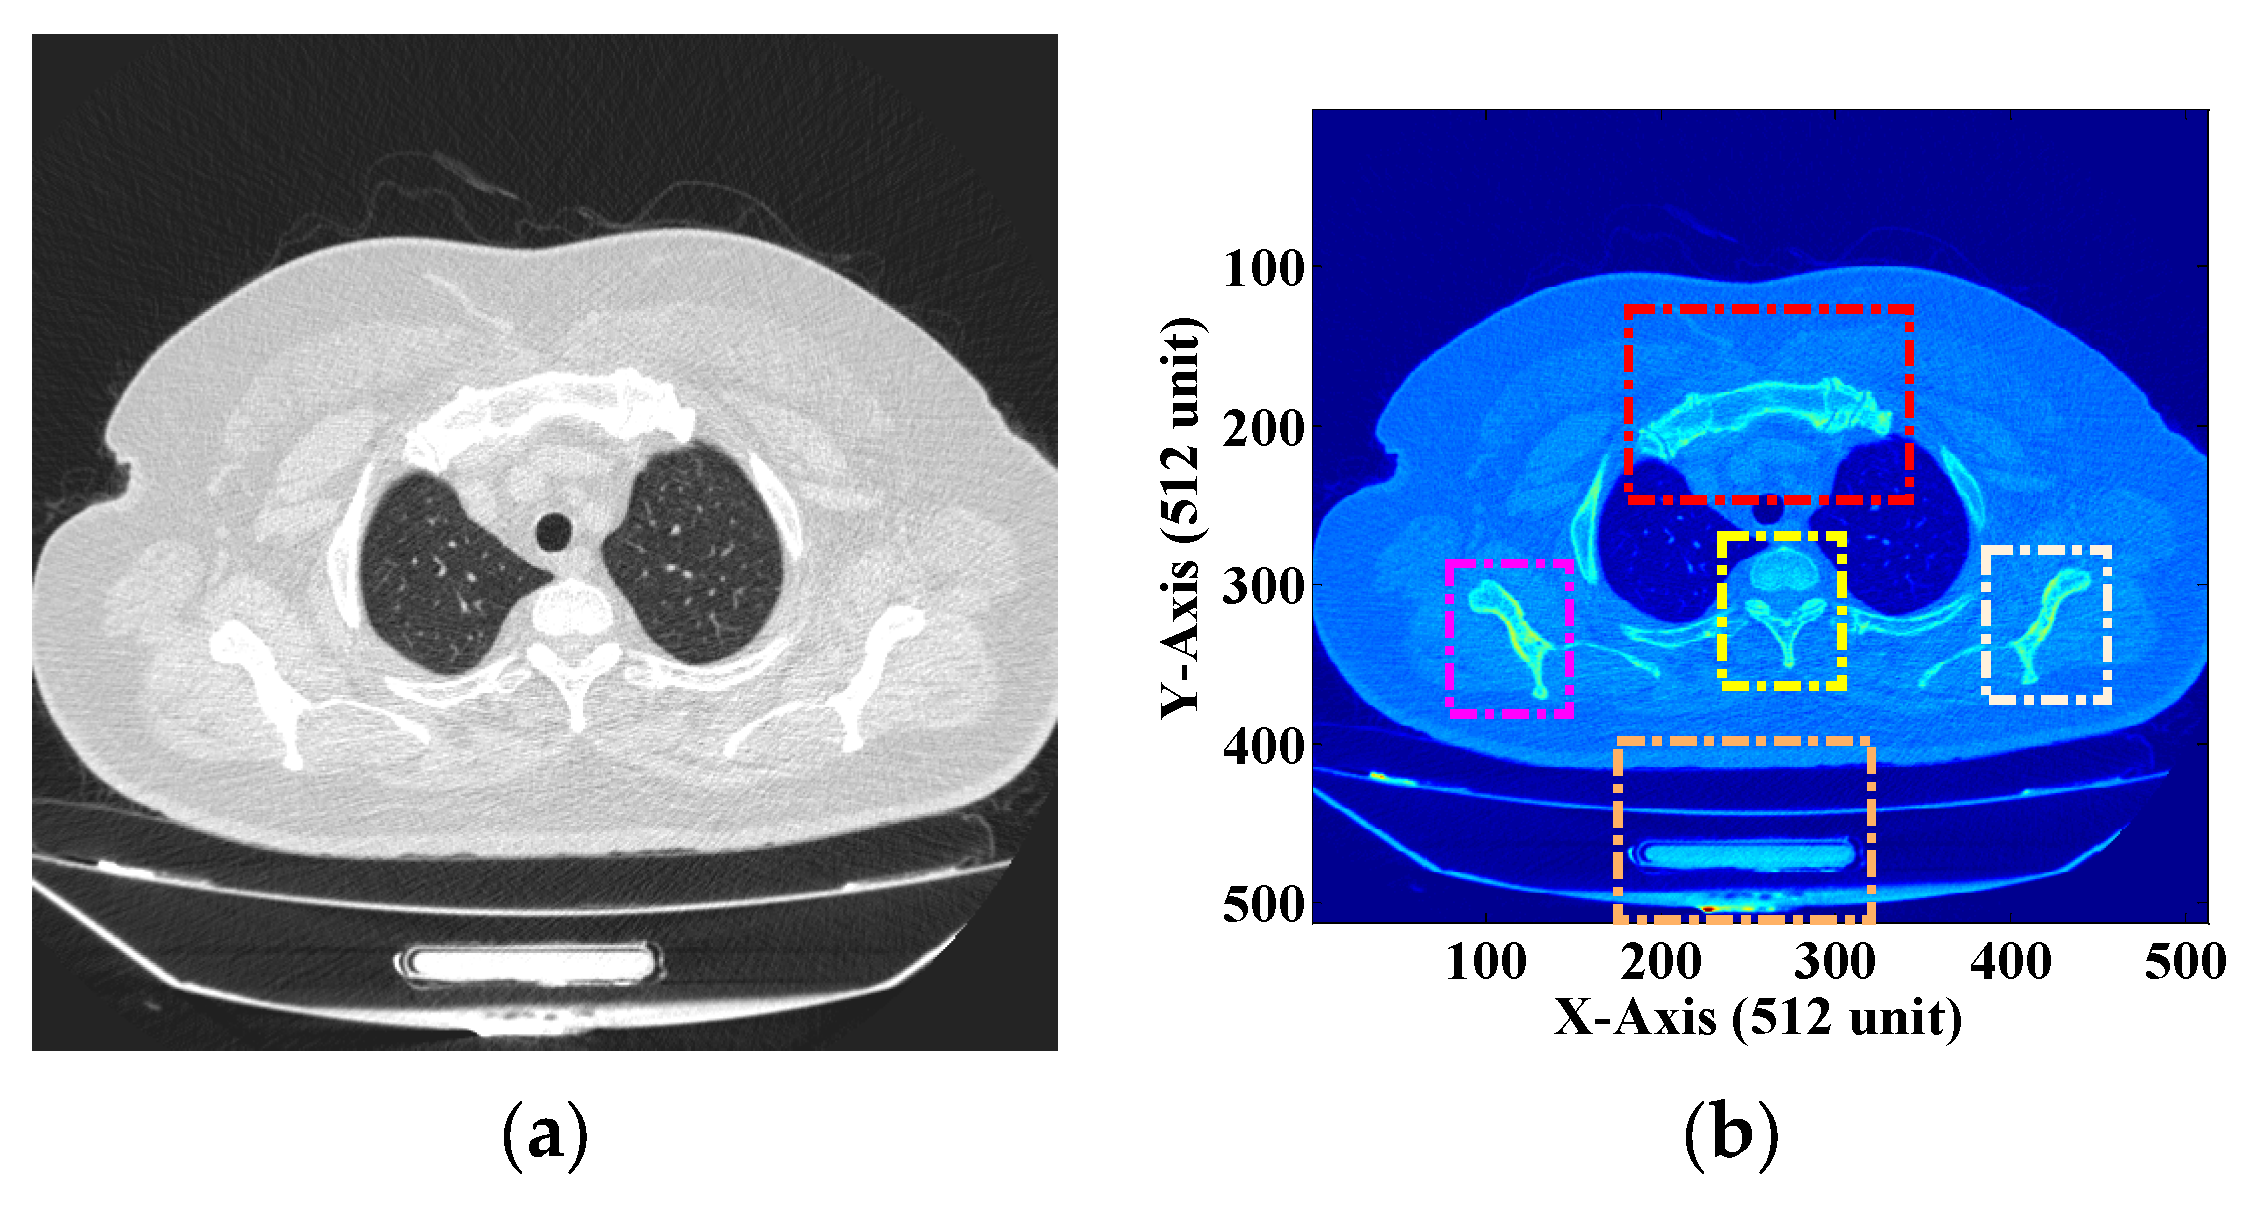

2.1. Mathematical Framework for Extraction of the ROI and NROI

3.1. ROI and NROI-Based Compression of the DICOM Image